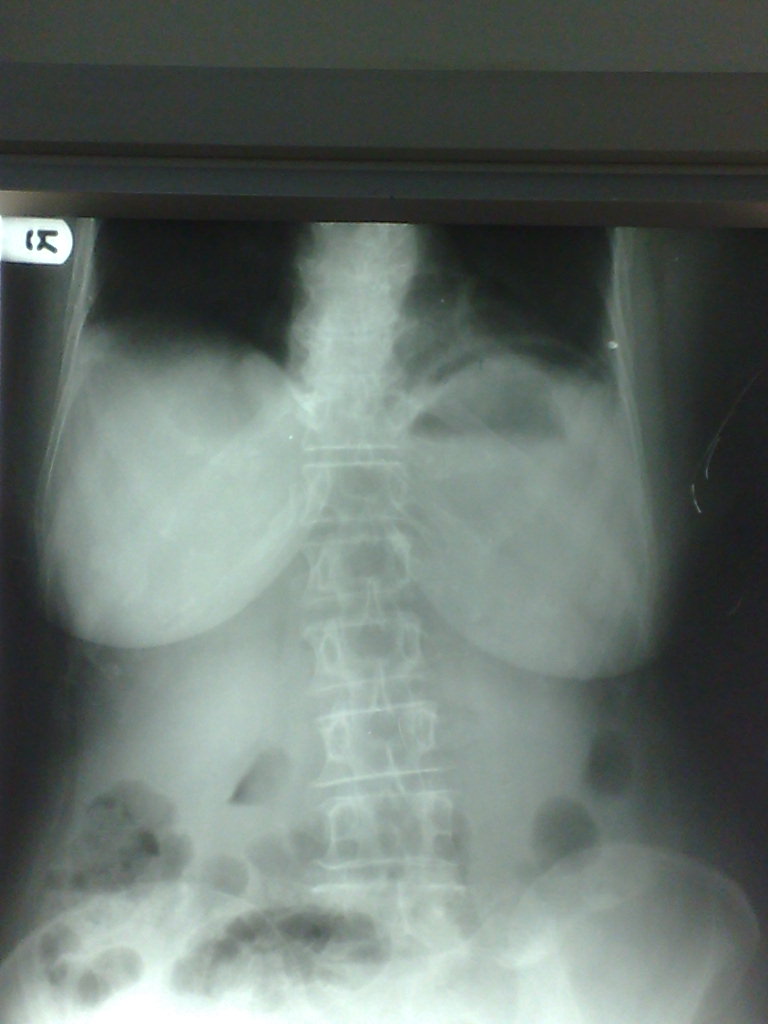

Abdominal xray showing free air under diaphragm. Download Scientific

Gas Under Diaphragm . This patient has a large volume of free gas under the diaphragm. A case report of a patient with gas under the right diaphragm, a rare radiographic. Dark crescents have formed separating the thin diaphragm. Pneumoperitoneum (aeroperitoneum is a rare synonym 12) describes gas within the peritoneal cavity, often due to critical illness. We report a case of gas under the diaphragm due to a ruptured. It should have appeared as follows: The most common cause of gas under diaphragm is hollow viscous perforation. This is a sign of bowel perforation. In 10% of cases it can be due to rare causes, both.

Xray of the chest and abdomen showing gas under the diaphragm Gas Under Diaphragm We report a case of gas under the diaphragm due to a ruptured. This is a sign of bowel perforation. This patient has a large volume of free gas under the diaphragm. Dark crescents have formed separating the thin diaphragm. Pneumoperitoneum (aeroperitoneum is a rare synonym 12) describes gas within the peritoneal cavity, often due to critical illness. A case. Gas Under Diaphragm.